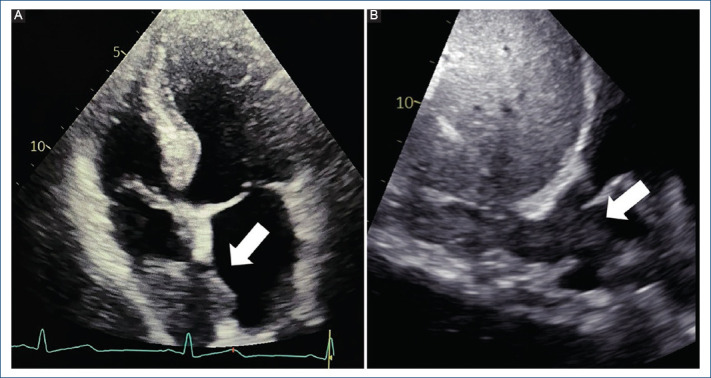

肝细胞癌伴下腔静脉肿瘤血栓延伸至心室1例。

Hepatocellular carcinoma with inferior vena cava tumor thrombus extending into cardiac chambers: case report.